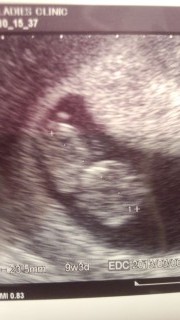

現在妊娠10w2dですが先日9w3dで撮った写真です!真っ正面を向いてカメラ目線な我が子に何とも・・・w

子宮内で出血があって薬を飲んだりとありましたが赤ちゃんは順調に育っているとのことでほっと一安心。日に日に大きくなっているであろうこの子がとても愛おしいです♪最近ではつわりが軽くなって来たので食事をする喜びもまた戻ってきました!

短い手足をぴくぴく動かしていました!頭と胴体がはっきりわかる様になり、7wの写真より随分成長していたので、先生にも「赤ちゃんの成長が素晴らしい!」と言って頂き嬉しかったです。